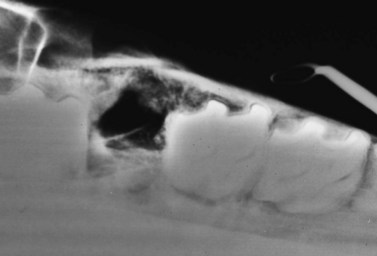

Removing dental fragments can be difficult because often no portion of the tooth is visible supra-gingivally, and because access to the apical aspect of the alveolus, especially one of a young horse, is poor using an oral approach. The dental fragments should be clearly identified on radiographs (Figs 20.26 & 20.27) and then, if possible, elevated per os using long, right-angled elevators (Fig. 20.28). After the fragments are loosened, they can be extracted with right-angled forceps; endoscopic guidance greatly facilitates their removal. When dental fragments or fractured teeth cannot be extracted orally, they can be repulsed using a special root fragment punch or Steinmann pin (Figs 20.2920.31). Radiographic or fluoroscopic guidance may aid the approach to the retained fragments. A 4-mm osteotomy is created over the retained fragment using a Steinmann pin or drill bit, and the Steinmann pin or a root fragment punch is inserted into the osteotomy so that it contacts the fragment. If the pin or punch is positioned properly, the fragment can usually be repulsed into the oral cavity with little force. The alveolus is cleaned of debris, using a spoon curette, and irrigated. The skin incision over the osteotomy is left unsutured to heal by second intention.

Fig. 20.27 Radiograph showing dental fragment in the apex of a mandibular alveolus. The tooth was fractured during an attempt at extraction per os. Dental fragments in the alveolus of a young horse can be difficult to remove, but with careful perioperative imaging to ensure accuracy of the placement of the punch, the fragment can be repulsed into the oral cavity with the horse sedated after desensitizing the affected region with a regional nerve block.